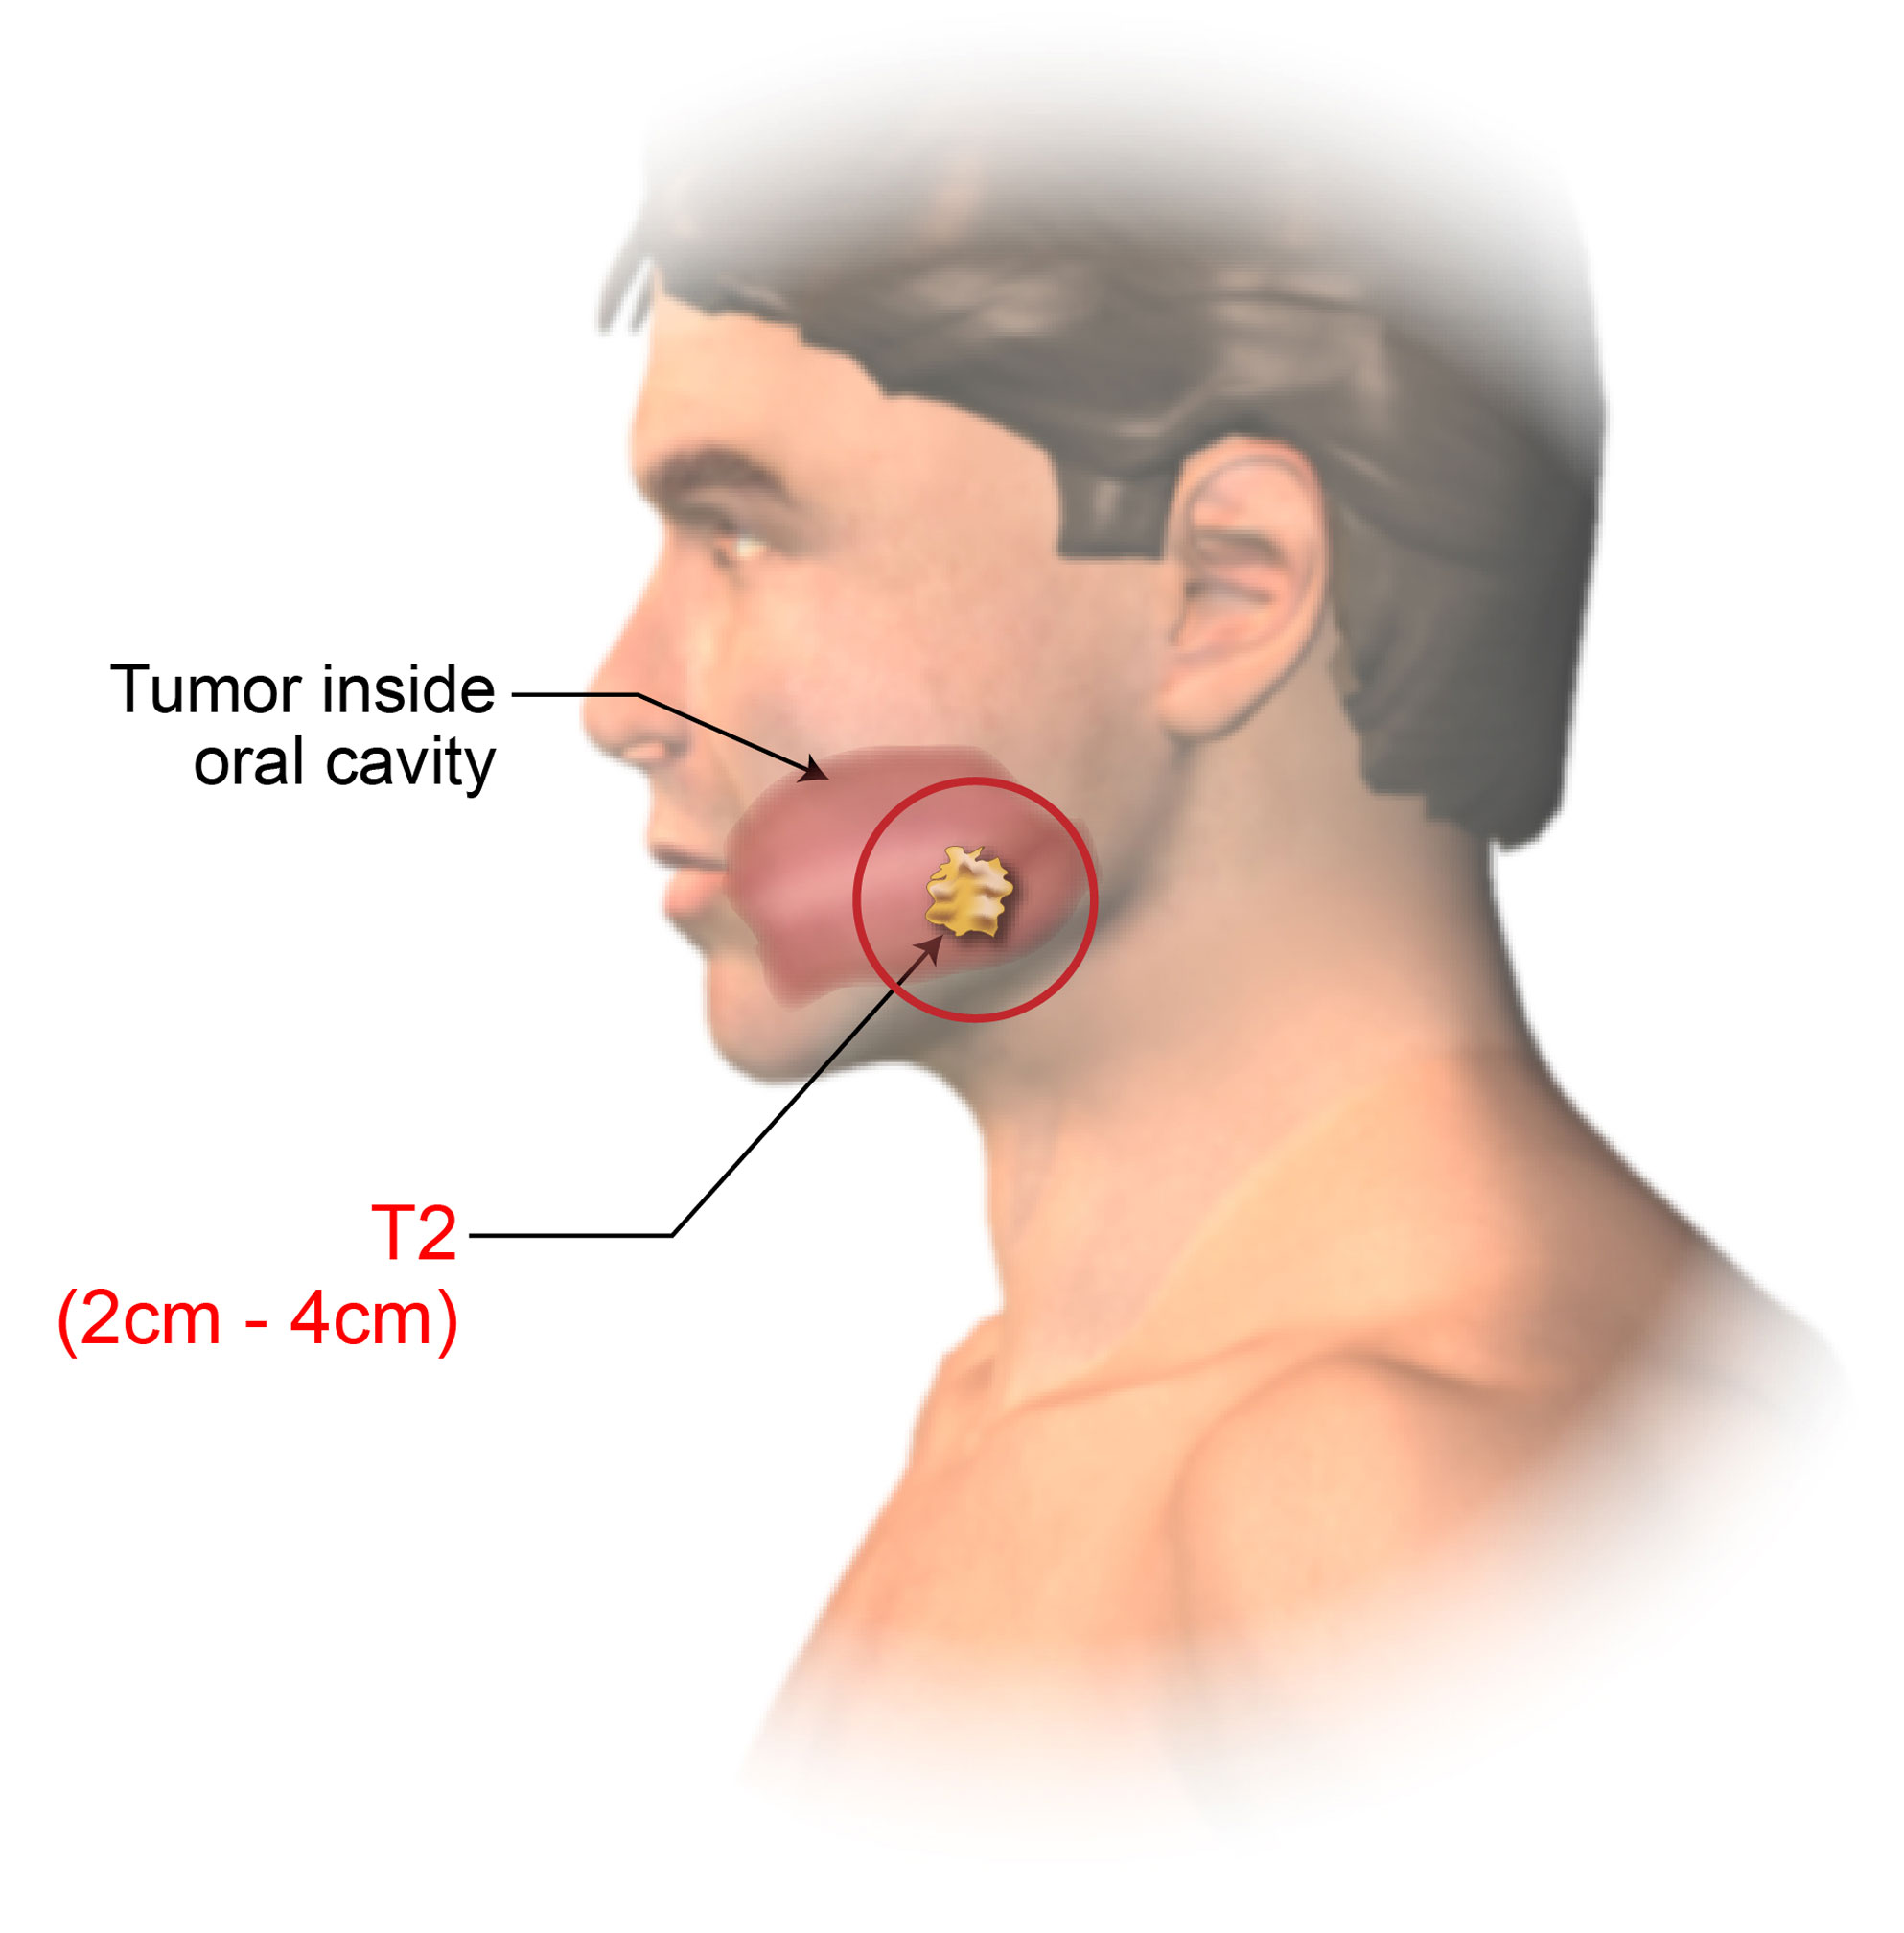

Oral Cancer Mouth Cancer Anatomy Headandneckcancerguide Org

Stages Of Oral Cancer Mouth Cancer Headandneckcancerguide Org

Staging Of Lip And Oral Cavity Cancer American Head Neck

Stages Of Oral Tongue Cancer Headandneckcancerguide Org

Understand How Oral Cancer Is Staged And Graded Ctca